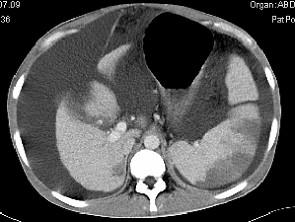

问题 患者男,29岁,乙肝病史10余年,腹胀,有移动性浊音,影像检查如图,最全面的诊断是 ( )

选项 A、大网膜膈下间位及脾梗 B、胆结石及脾梗 C、肝硬化腹水 D、肝硬化腹水、脾梗、胆囊结石 E、肝硬化

答案 D